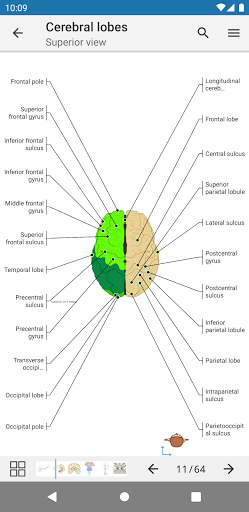

- The anatomic view now displays more labels

-The pins mode have a new behaviour allowing you to follow an anatomical structure much more easily

-You can now manually select the font size you prefer for your anatomical structures labels (in labels mode)